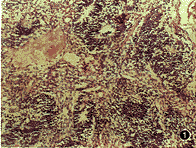

病理检查:肿瘤为灰白色碎块组织,附有血凝块,总体积为1.3 cm×1.3 cm×0.6 cm,质脆。镜下检查:肿瘤由幼稚的不成熟的胚胎组织构成,瘤细胞异型性明显,核分裂象多见。可见神经母细胞围绕腔隙排列成酷似原始神经管的结构(图1),幼稚的鳞状上皮巢。幼稚的软骨(图2)及幼稚的呼吸上皮、消化道上皮等。

图1 示幼稚的神经组织,神经母细胞围绕腔隙排列成酷似原始神经管的结构 HE×117

图2 示幼稚的软骨、幼稚的鳞状上皮巢 HE×117